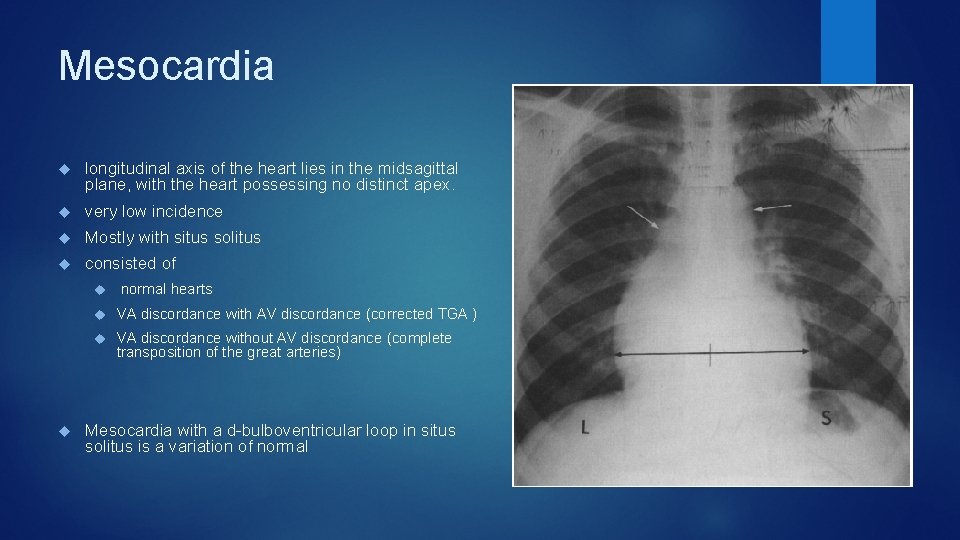

Mesocardia longitudinal axis of the heart lies in the midsagittal plane, with the heart possessing no distinct apex. very low incidence Mostly with situs solitus consisted of normal hearts VA discordance with AV discordance (corrected TGA ) VA discordance without AV discordance (complete transposition of the great arteries) Mesocardia with a d-bulboventricular loop in situs solitus is a variation of normal